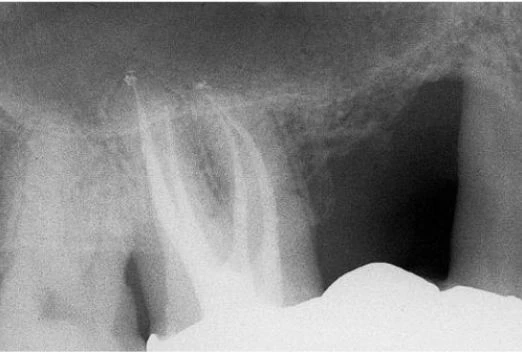

Hiếm khi thấy một ống tủy chia đôi ở 1/3 chóp thành hai ống tủy nhỏ hơn với những lỗ chóp riêng biệt (Weine’s type IV) (hình 11.38). Thông thường có một đoạn cong ở phía trong hoặc phía xa ở 1/3 chóp chân răng (hình 11.39). Sự hiện diện của đoạn cong vào trong của răng cửa bên giải thích tại sao những tổn thương có nguồn gốc nội nha của răng cửa bên thường biểu hiện ở vùng khẩu cái (hình 8.21, 8.27).

Hình 11.38. Phim trong lúc điều trị của răng cửa giữa cho thấy hình ảnh giải phẫu của răng cửa bên gần đó đã được điều trị nội nha. Hình ảnh X-quang cho thấy ống tủy chính chia làm hai ống tủy nhỏ hơn ở đoạn gần chóp, mỗi ống tủy có một lỗ chóp riêng. Việc trám bít hai ống tủy này xảy ra tự nhiên trong khi trám ống tủy chính.

Hình 11.39. Phim sau điều trị của 1 răng cửa bên trên với 1 đoạn cong về phía xa ở 1/3 chóp.